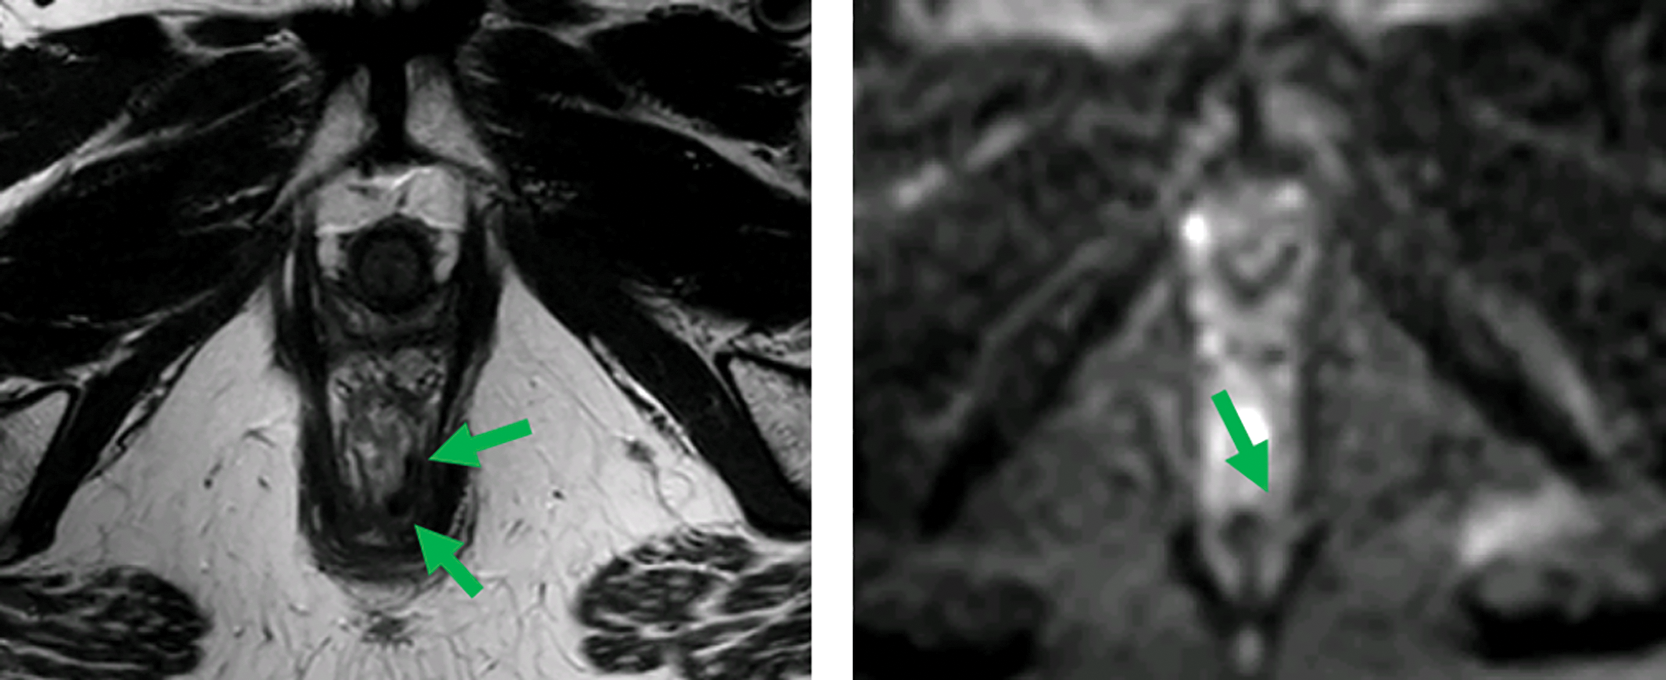

Figure 1

MRI before (top) and after (bottom) neoadjuvant therapy. Axial T2‑weighted and b1000 DWI images show a distal rectal tumor (red arrows). After neoadjuvant therapy, a T2 dark, fibrotic remnant is seen without restricted diffusion (green arrows), indicative of a clinical complete response.